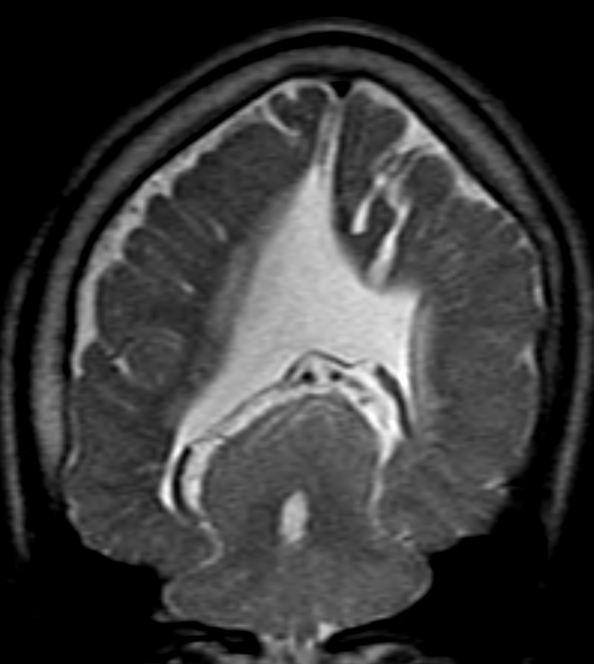

Sweep the Midline: What parts are missing?

Run the Rim…where is the cortex “too thick?”

“Missing”=disorganized rostrum, genu, anterior body of the corpus callosum Cortex of the anterior medial frontal lobes “too thick” with fused grey matter across the anterior midline where the “genu” should be.